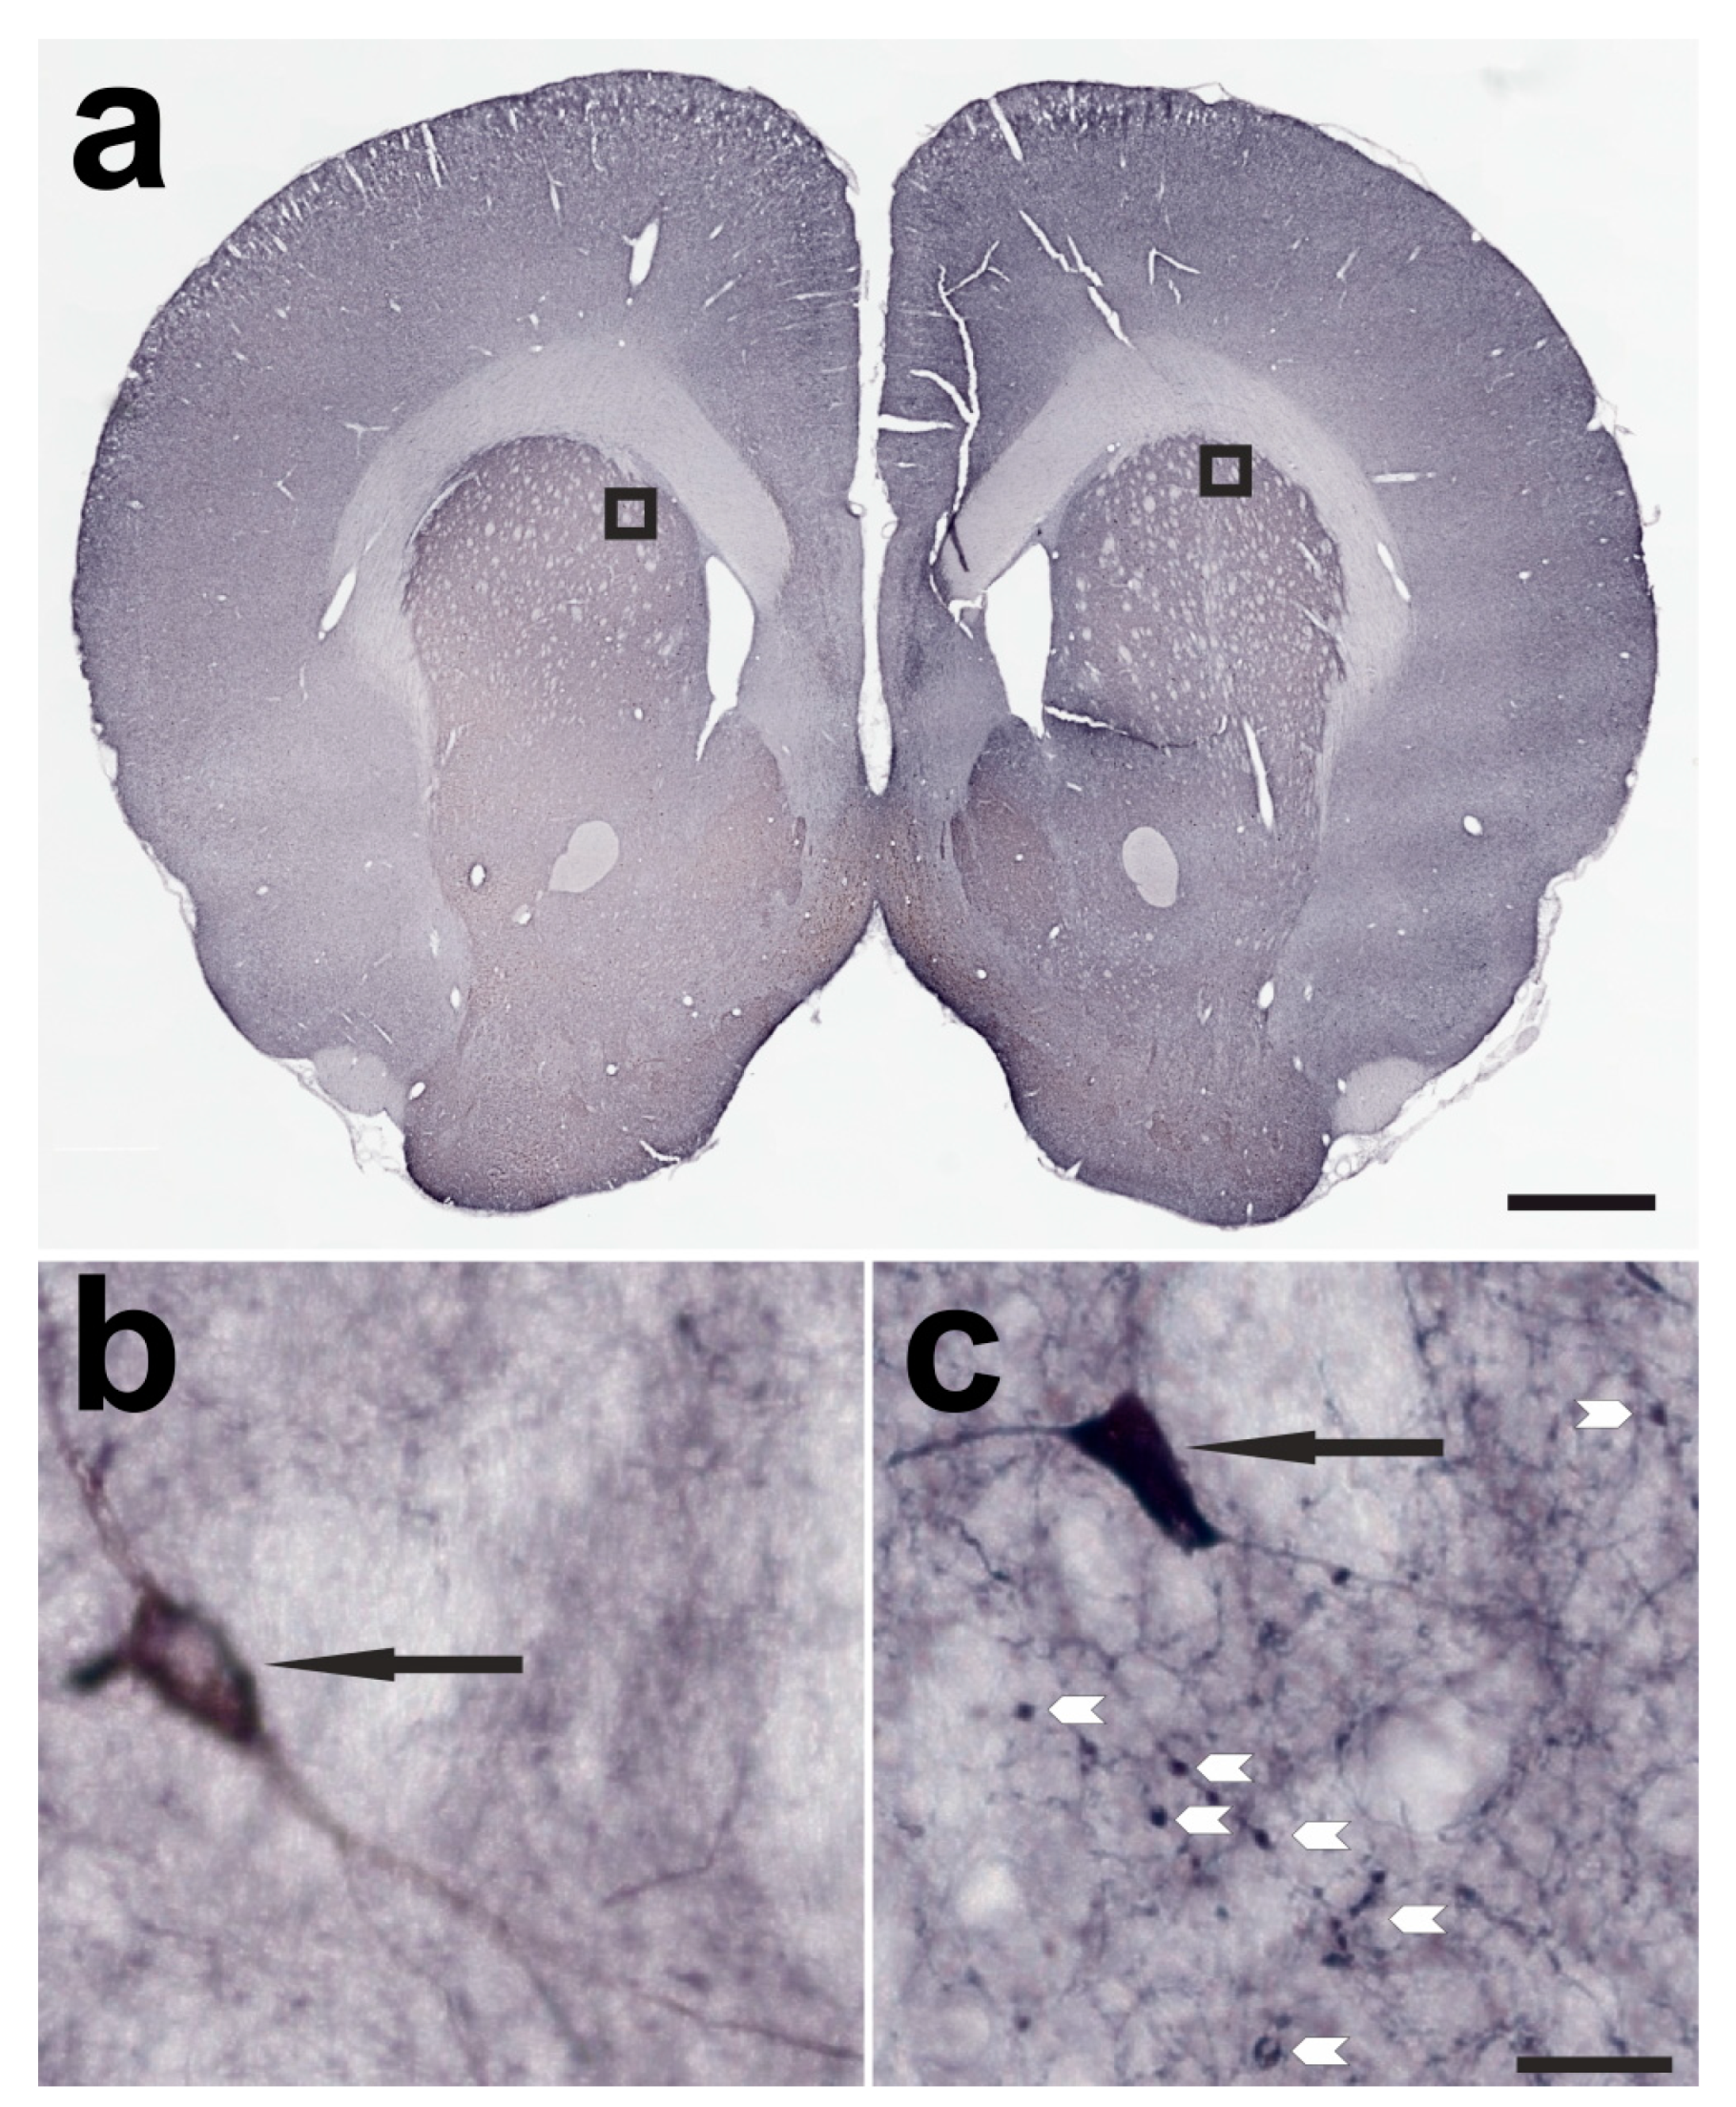

2.1. Verification of Successful BoNT-A Injection—Botulinum Neurotoxin-A-Induced Varicosities